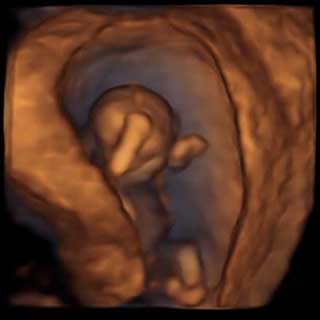

تصویر سه بعدی هفته یازدهم بارداری

نیمی از اندازه سر ایجاد شده است. انگشتان دست و پا هم کاملا مجزا شده اند و در پایان هفته ۱۱ ام تمام ۲۰ انگشت را می توان مجزا در نظر داشت.

در این زمان استخوان های کودک هم سفت می شود ولی پوست بدن همچنان نازک است. کودک شما بسیار فعال است ولی متاسفانه آن قدر کوچک است که هنوز توسط مادر این حرکت و جنب و جوش احساس نمی شود.

در اطراف جنین مایع آمنیوتیک وجود دارد و کودک می آموزد که چگونه بلع انجام دهد. اعضای بدن به رشد خود ادامه می دهند و برخی از این اندام ها عملکرد خود را پیدا می کنند.

در طی ۳ هفته بعدی، اندازه جنین 2 برابر می شود. در جفت، عروق خونی بیشتری ایجاد می شود تا اکسیژن و ریزمغذی های مورد نیاز جنین شما را که برای رشد می خواهد، فورا در اختیار آن قرار دهد. گوش ها در محل صحیح خود قرار می گیرند، از سمت گردن به محلی در سر.